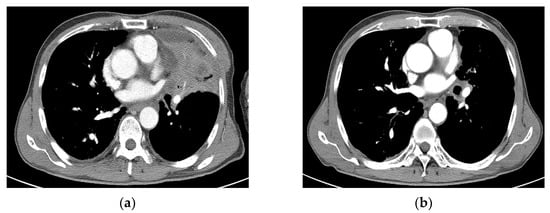

3.5. PD and a Case of Fatal Hemoptysis

4. Discussion